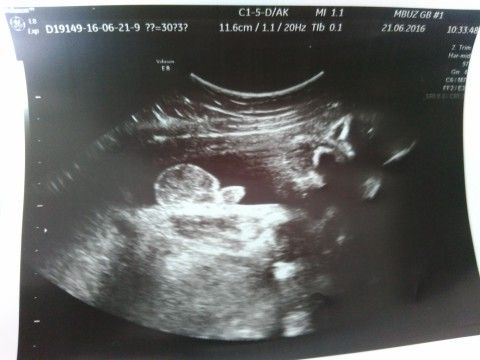

Часто вижу тут посты вроде " У меня 12-22 недели, сказали пол, а может быть что это ошибка?" Может! 31 неделю называли ребёнка дочкой (даже кое что розовое моя мама прикупила ;) ) Девы, прошла 3й скрин. Сынок :D показали штырек со всех сторон, и мошонку, теперь ошибки быть не может))

Нам тоже сказали сынок. Как во второй, так и в третий раз. Поздравляю. И фото дали на память. Для достоверности)))